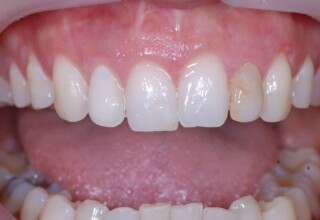

Αποκατάσταση διαστημάτων μεταξύ κεντρικών και πλαγίων τομέων

Τα διαστήματα έχουν δημιουργηθεί κυρίως λόγω των στενών πλαγίων. Μετά την ολοκλήρωση της ορθοδοντικής θεραπείας τα διαστήματα “έκλεισαν” με την τοποθέτηση δύο αποκαταστάσεων σύνθετης ρητίνης.